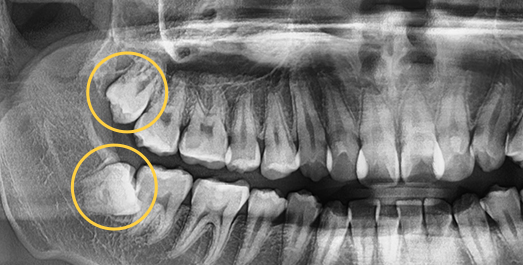

Some wisdom teeth erupt normally, but others may erupt at an angle, horizontally, or remain fully impacted. Wisdom teeth that do not erupt properly can disturb the dental arch and are difficult to clean, which may lead to decay of adjacent molars. In such cases, extraction is recommended.

• Horizontally

impacted wisdom tooth

• Angulated

• Vertically